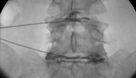

Im Zentrum für Wirbelsäulenchirurgie und Schmerztherapie wird das gesamte Behandlungsspektrum bei Erkrankungen, Unfällen und Schmerzsyndromen der Hals-, Brust- und Lendenwirbelsäule sowie der angrenzenden Strukturen bei Kindern und Erwachsenen in interdisziplinärer Vorgehensweise abgedeckt. Rund um die Uhr besteht die Möglichkeit der Maximalversorgung. Häufig erfolgt die Therapie nach einem Stufenschema, bei dem versucht wird, mit weniger eingreifenden Maßnahmen zu beginnen. Je eingreifender die Therapie, umso höher ein theoretisches Risiko des Auftretens negativer Nebeneffekte.

Insgesamt steht die Behandlung von Verschleißerkrankungen im Vordergrund. Des Weiteren werden im Zentrum jegliche Arten von z. B. Unfällen, Infektionen, Tumoren und Metastasen, Deformitäten, rheumatischen und angeborenen Erkrankungen bei Erwachsenen und Kindern behandelt. Jährlich erfolgen neben den konservativen mehr als 15.000 interventionelle Maßnahmen sowie mehr als 3.000 Operationen. Wenn möglich werden minimalinvasive oder bewegungserhaltende Verfahren angewendet.